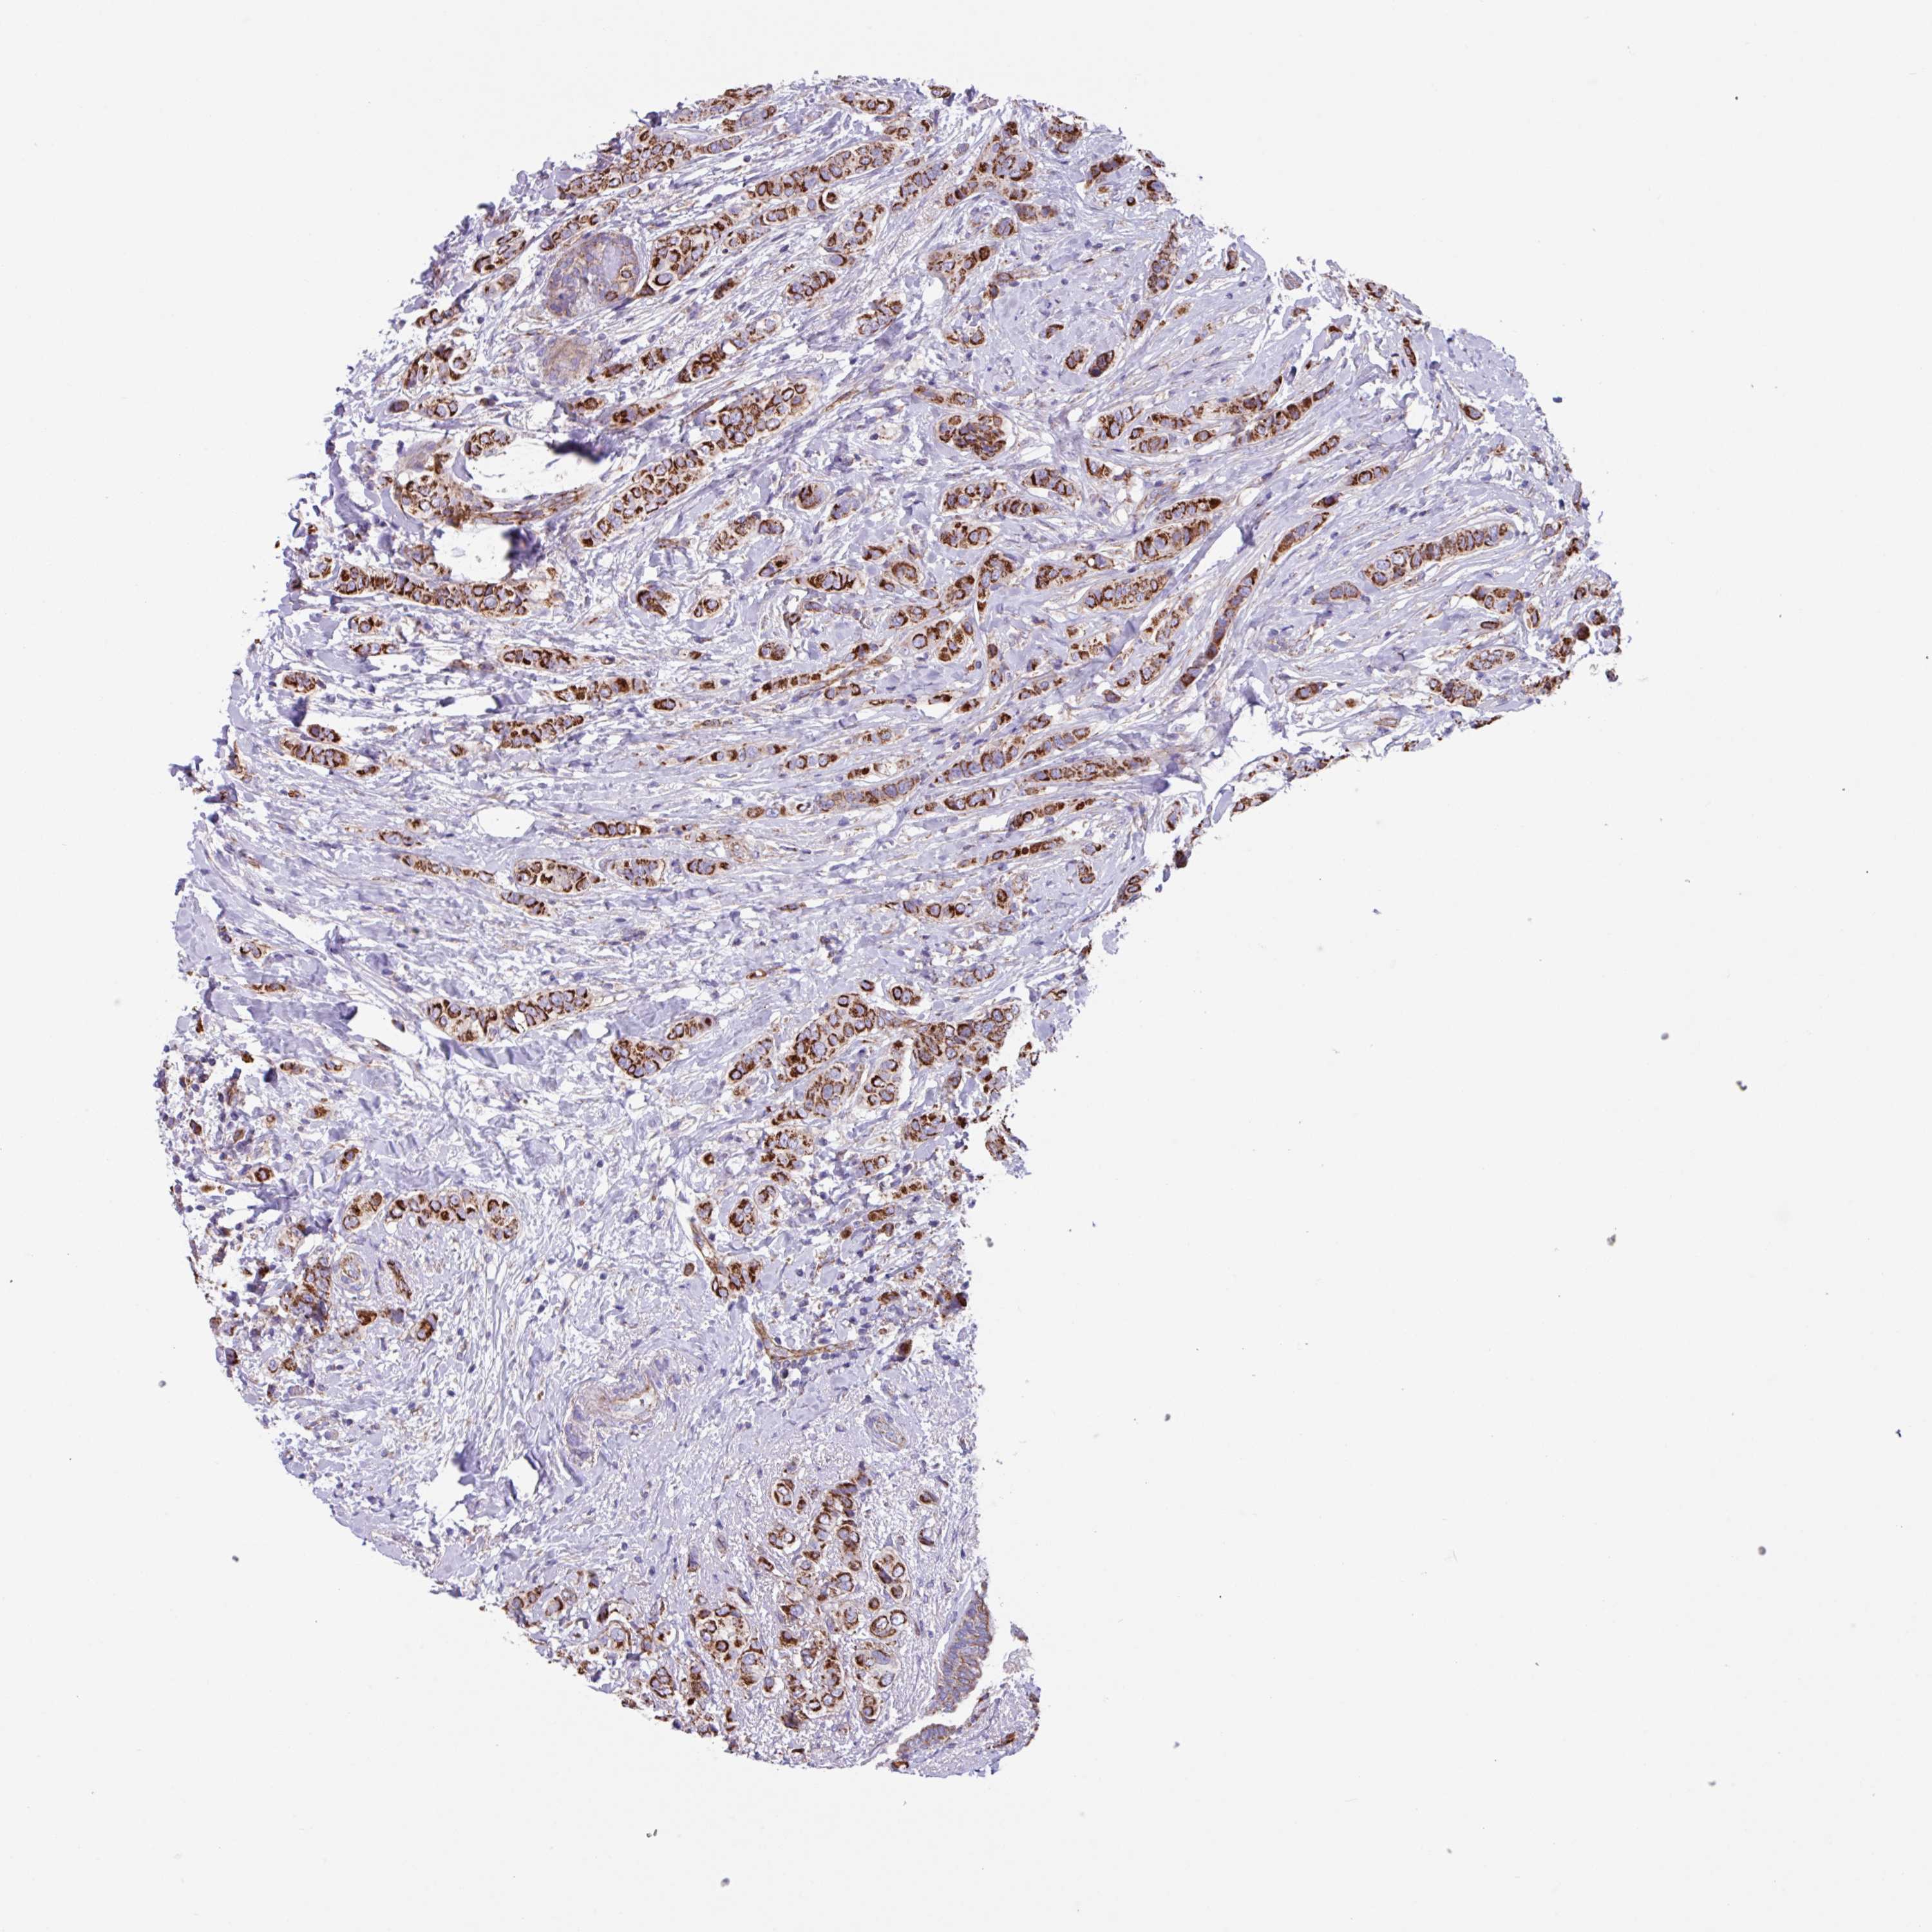

CANCER BREAST CANCER Show tissue menu

BRCA TCGA BRCA VALIDATION PROTEIN EXPRESSION

Breast cancer

Human cancer

OTULIN is not prognostic in Breast Invasive Carcinoma (TCGA)